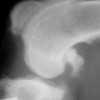

(aka ‘Arthritis’, ‘Rheumatism’, DJD) What is osteoarthritis? Arthritis means ‘inflammation of a joint’. Inflammation is a basic way the body reacts to infection, irritation or trauma and we generally see redness, swelling, warmth and pain. So ‘arthritis’ is actually not a very specific term and there are a number of quite different problems that will […]